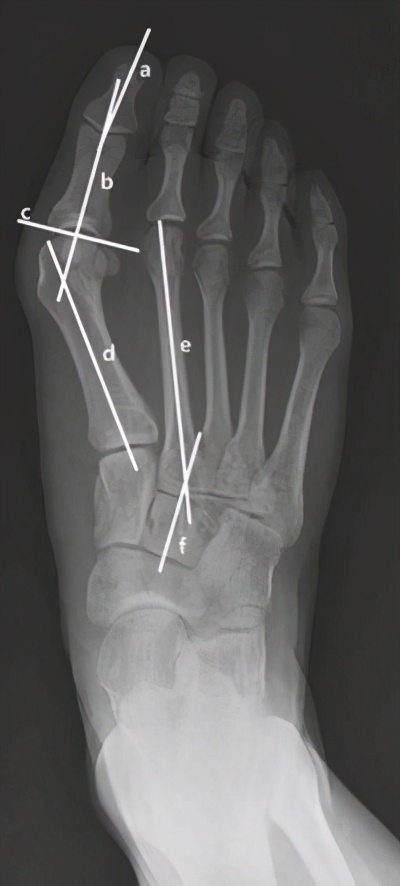

大脚骨X线

做拇外翻的临床辅助检查很简单,就是拍个DR,我们通过脚的X线可以清楚看出来拇外翻的情况以及轻重程度。为了清除看到双脚骨头分布情况,我建议拍正位片的时候需要拍双足负重正位片,以便为后续手术做良好的指导。